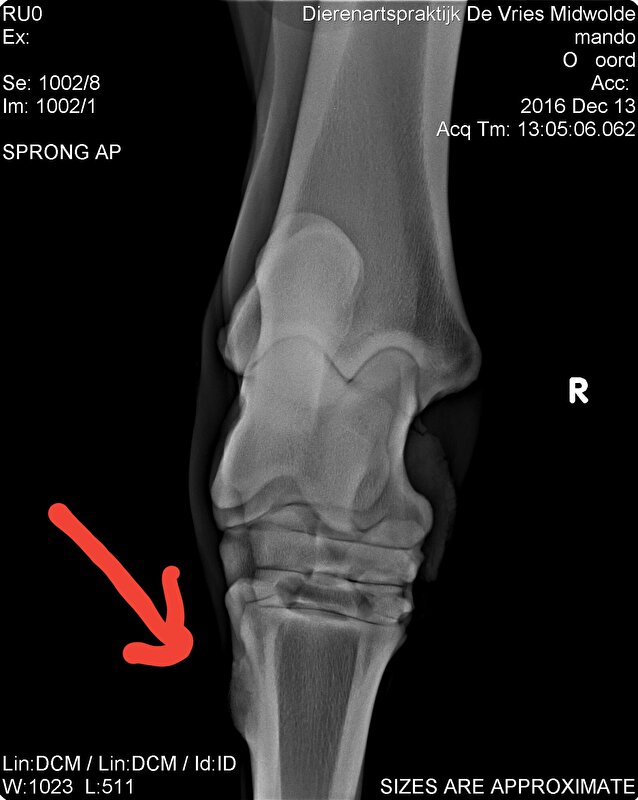

Hier zie je hem zitten